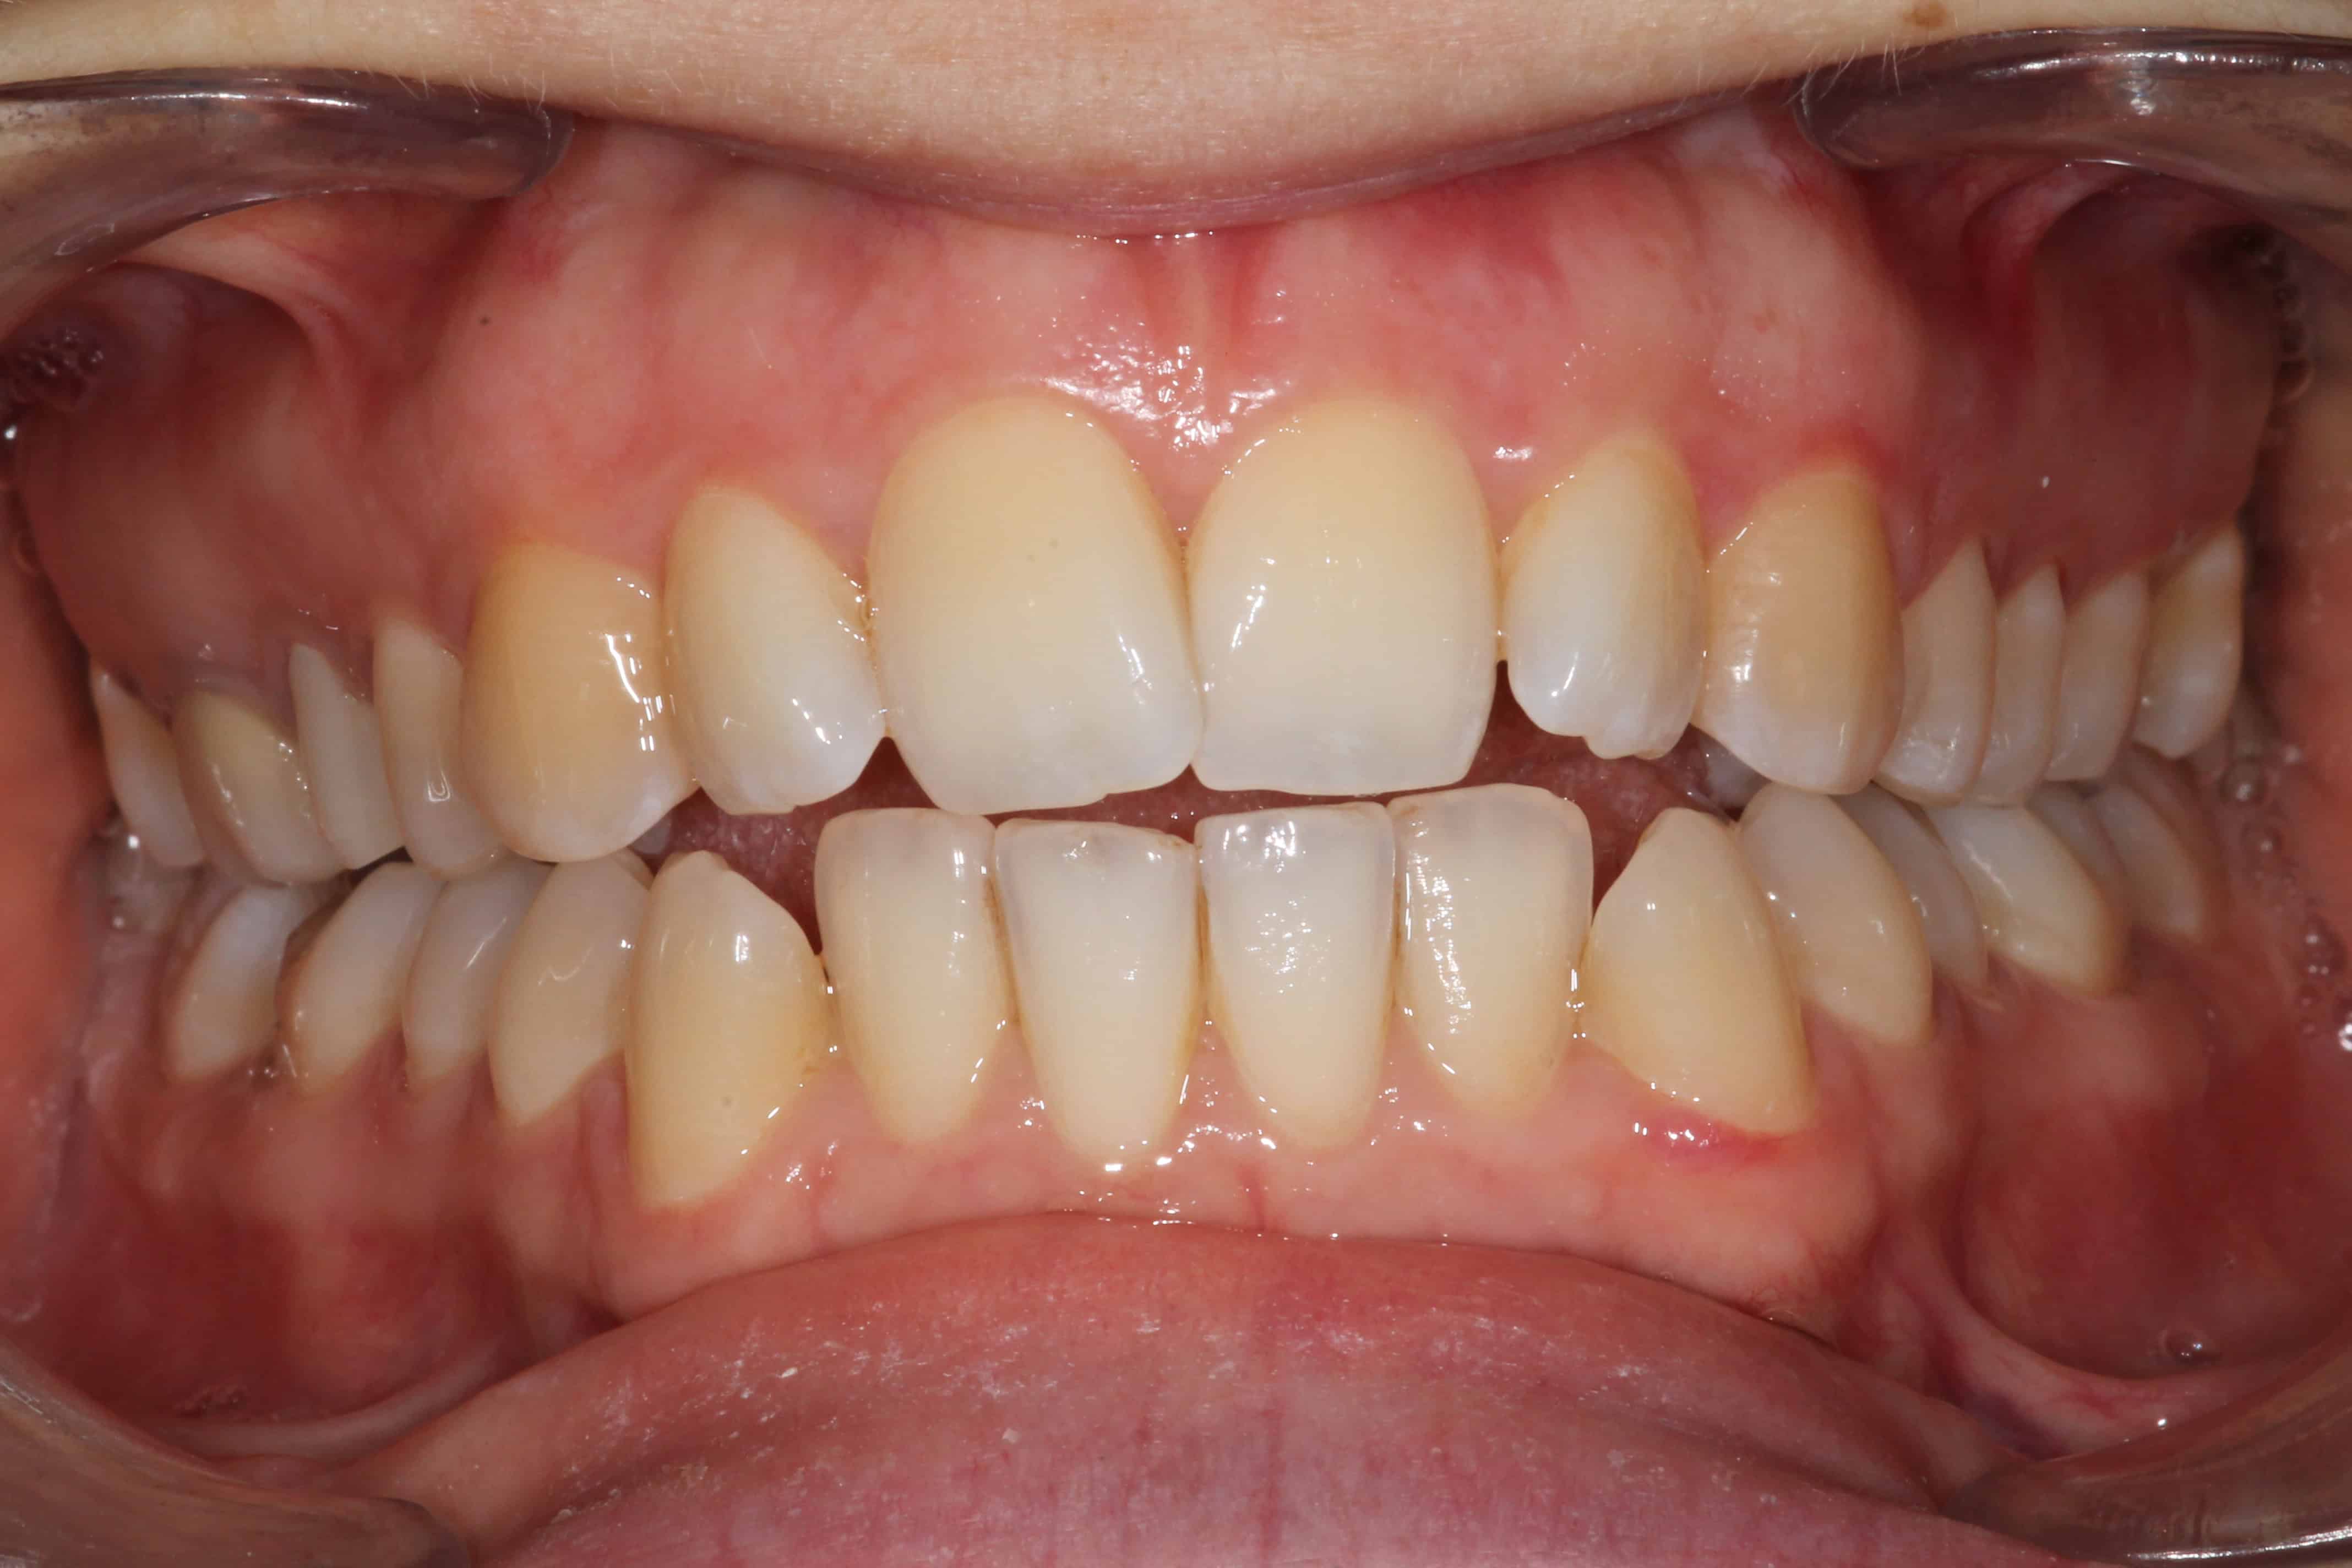

Exemple de cas :